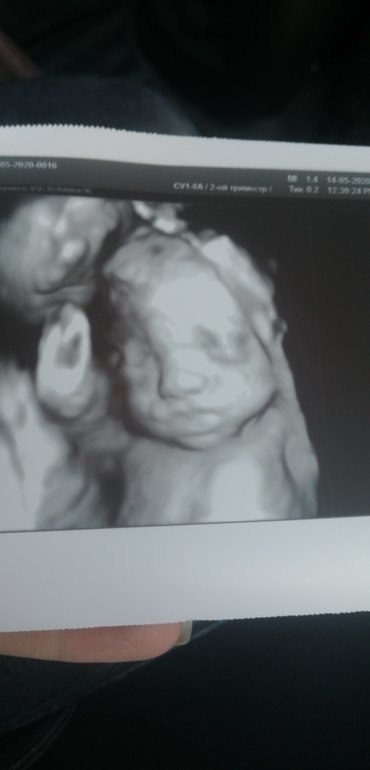

УЗИ 26 недель🙂

Какая малышка сладкая🤗 Фото очень удачное.

😍😍😍хорошо получилось)